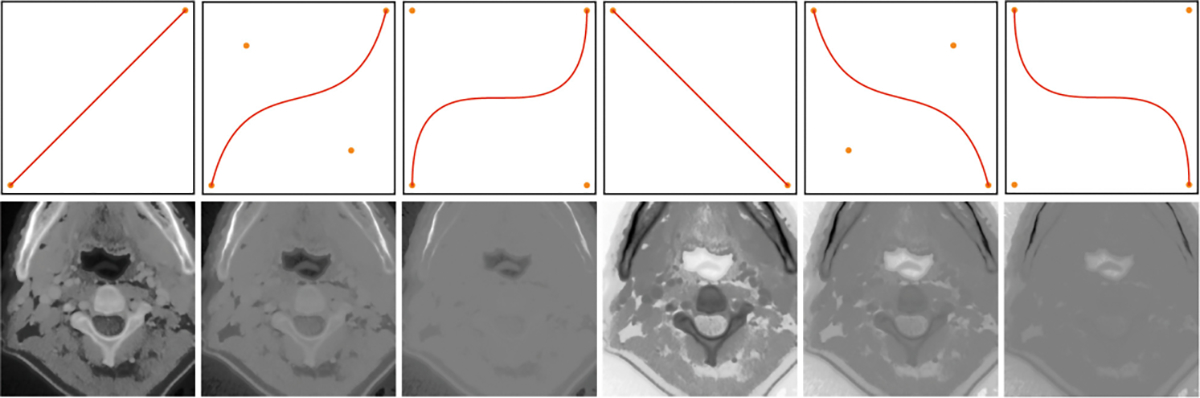

Head and neck tumors and metastatic lymph nodes are crucial for treatment planning and prognostic analysis. Accurate segmentation and quantitative analysis of these structures require pixel-level annotation, making automated segmentation techniques essential for the diagnosis and treatment of head and neck cancer. In this study, we investigated the effects of multiple strategies on the segmentation of pre-radiotherapy (pre-RT) and mid-radiotherapy (mid-RT) images. For the segmentation of pre-RT images, we utilized: 1) a fully supervised learning approach, and 2) the same approach enhanced with pre-trained weights and the MixUp data augmentation technique. For mid-RT images, we introduced a novel computational-friendly network architecture that features separate encoders for mid-RT images and registered pre-RT images with their labels. The mid-RT encoder branch integrates information from pre-RT images and labels progressively during the forward propagation. We selected the highest-performing model from each fold and used their predictions to create an ensemble average for inference. In the final test, our models achieved a segmentation performance of 82.38% for pre-RT and 72.53% for mid-RT on aggregated Dice Similarity Coefficient (DSC) as HiLab. Our code is available at https://github.com/WltyBY/HNTS-MRG2024_train_code.